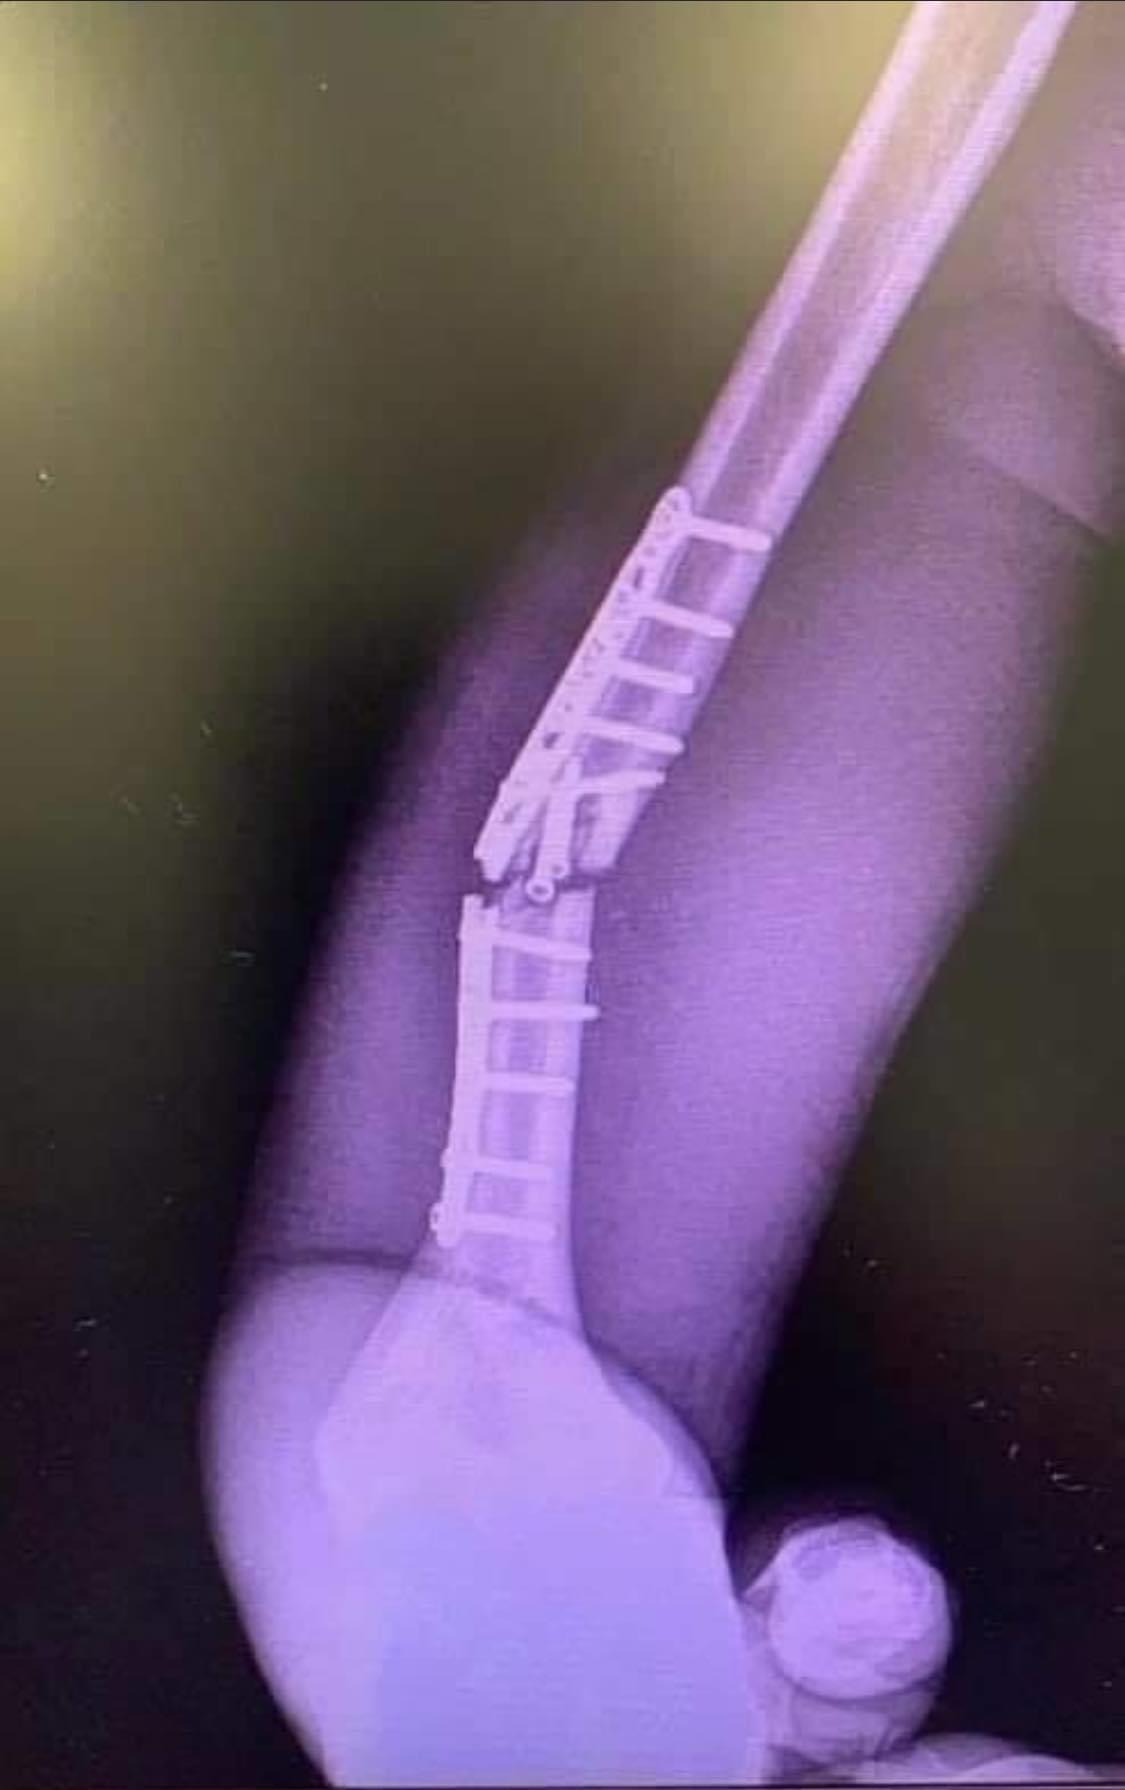

Gestern die zweite Op fuer MM93 wegen gebrochenener titan Fixur. Damit faellt er aus. Bradl ersetzt MM93.

...puhhh, das Bild sieht ja mal echt übel aus.kaneun hat geschrieben:Gestern die zweite Op fuer MM93 wegen gebrochenener titan Fixur. Damit faellt er aus. Bradl ersetzt MM93.

Das ist wohl dezent untertrieben.„Der Fahrer hatte bisher keine Schmerzen. Er hat sich immer an den medizinischen Rat gehalten und auf das Gefühl seines Körpers gehört. Unglücklicherweise hat zu viel Belastung dieses Problem ausgelöst“